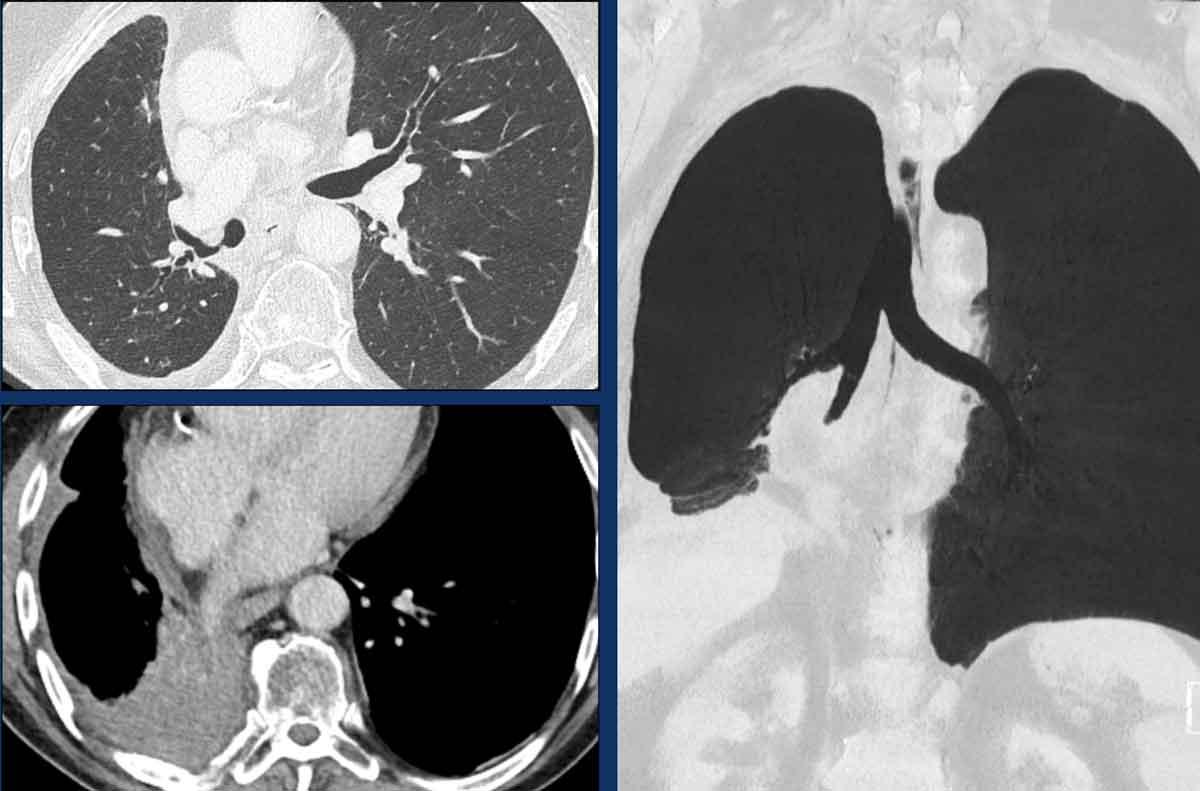

Hình ảnh

Teo phế quản ở thùy dưới phổi trái ở nữ giới 47 tuổi.

Cấu trúc phân nhánh điển hình với nhu mô phổi sáng xung quanh, đại diện cho phế quản giãn rộng chứa đầy chất nhầy (mũi tên).

Không có lỗ vào của phế quản phân thùy đáy sau (LB10) và ứ khí lan rộng của nhu mô phổi liên quan, thấy rõ nhất trên các tái tạo phổi.

Tiếp tục với hình ảnh tiếp theo…

Hình ảnh MIP (chiếu cường độ tối đa) lát dày cho thấy các đường thở giãn rộng chứa đầy chất nhầy ở thùy dưới phổi trái (mũi tên).